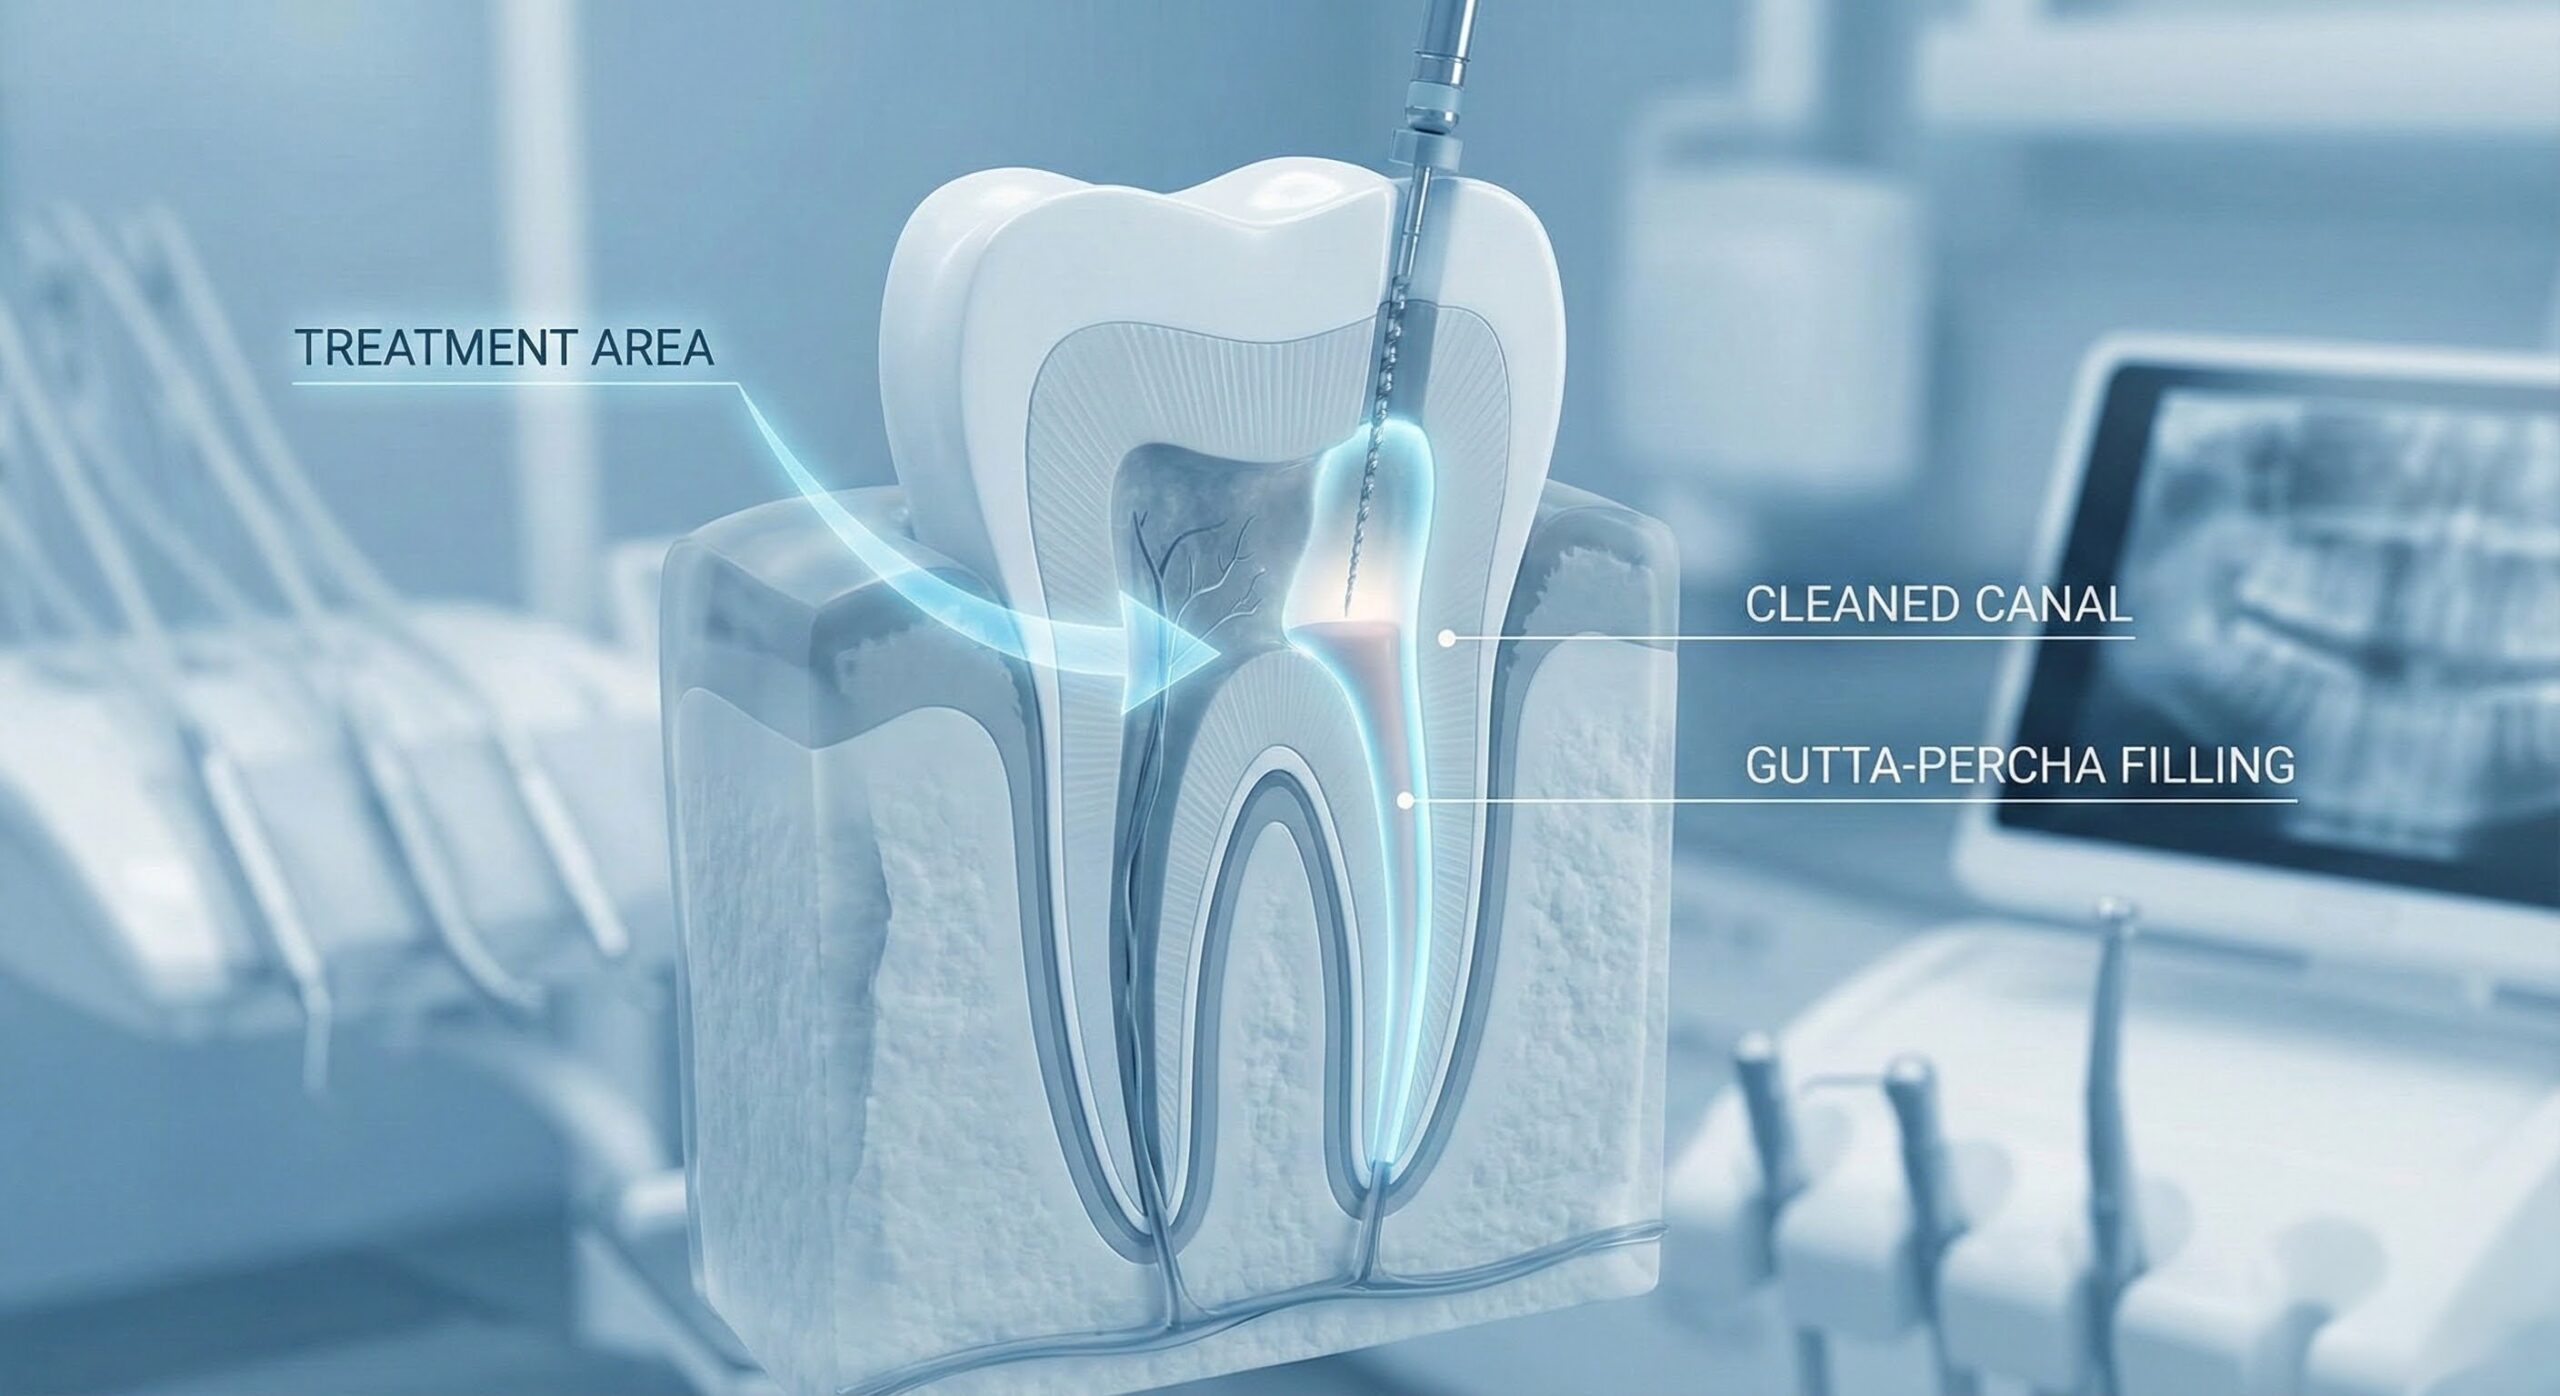

Dr. Rathore’s Dental is a friendly and trusted dental clinic in Noida Extension. We believe good dental care starts with listening, so we take time to understand your concerns and explain treatments in simple words. With modern equipment and caring doctors, we focus on making every visit comfortable while helping you achieve a healthy, confident smile.